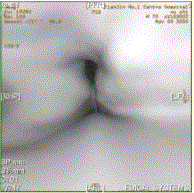

患者男,60岁,声音嘶哑半年,CT表现如下图。诊断正确的是A.声门区喉癌B.声门上喉癌C.喉正常表现D.喉结核E.喉乳头状瘤F.喉憩室

问题 患者男,60岁,声音嘶哑半年,CT表现如下图。 诊断正确的是

选项 A.声门区喉癌 B.声门上喉癌 C.喉正常表现 D.喉结核 E.喉乳头状瘤 F.喉憩室

答案 A

解析 A